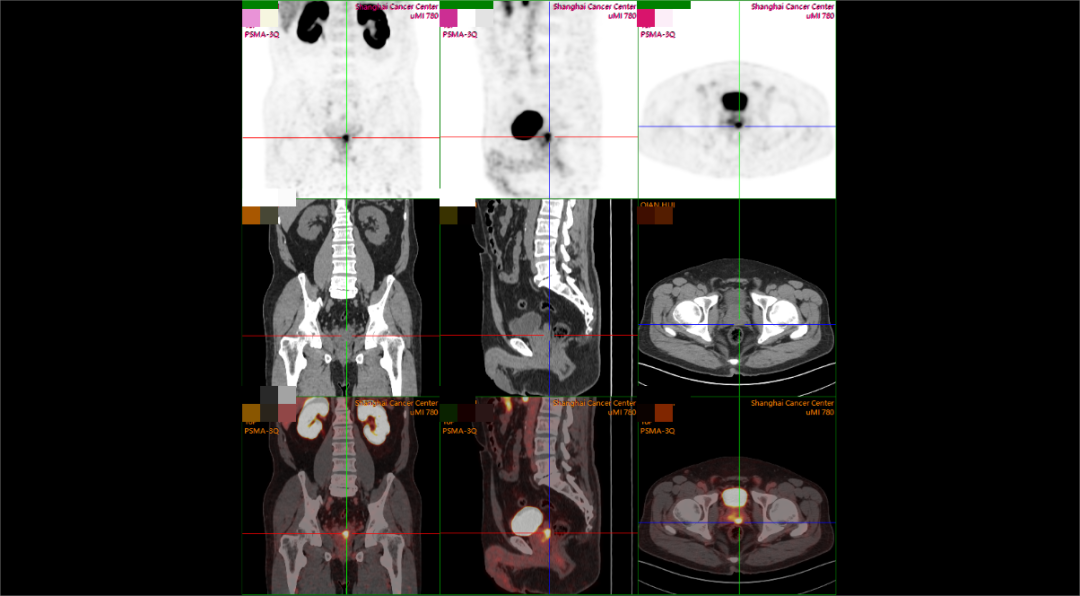

现病史:患者PSA 两年来持续升高,2025年10月PSA:8.68,外院MRI:pi-rads 2分。2025年10月10日我院穿刺,前列腺腺泡腺癌,Gleason评分:3+3=6,现为进一步诊疗入院。病理报告(2025.10.10):前列腺腺泡腺癌,GIeason评分:3+3=6 ;lSUP分组:1累及组织约20%;核医学报告(2025.10.16):前列腺形态欠规则,体积正常,最大横截面约4.6*3.6cm,左侧外周带PSMA摄取增高灶。